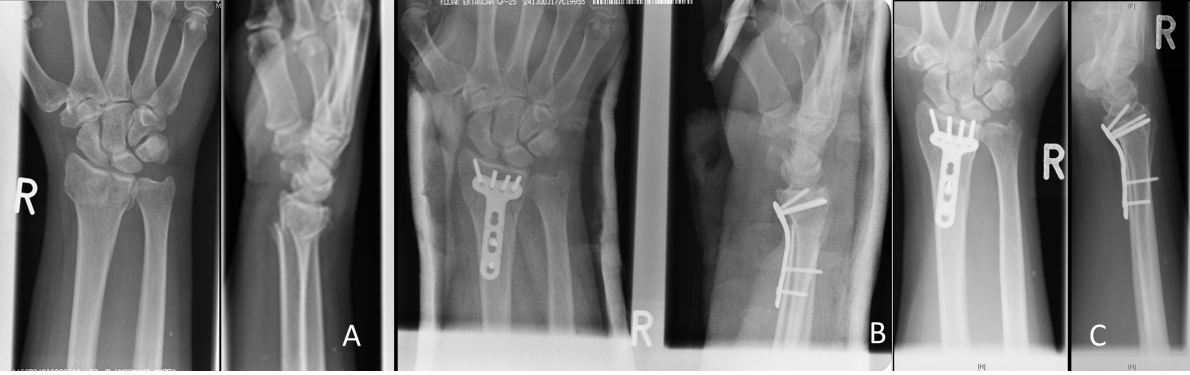

Figure 2: Radiographic follow-up series of a 52-year-old female patient with an AO 23C2 fracture, treated through a volar approach with 2.4 mm LCP (Synthes®). A) Posttraumatic x-ray. B) Follow-up radiographs after 12 weeks. C) Follow-up radiograph 16 months after trauma with no major loss of reduction.